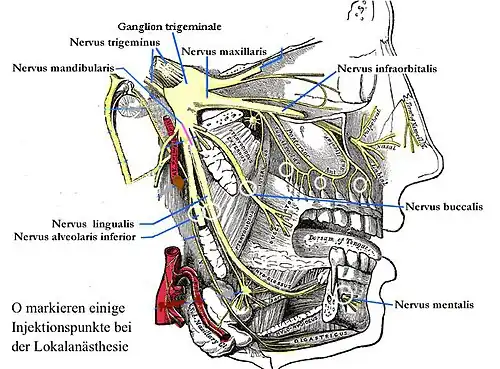

Die Lokalanästhesie (; lateinisch locus „Ort“, altgriechisch ἀν an „ohne“ und αἴσθησις aisthēsis „Wahrnehmung“ mit Alpha privativum, demnach örtliche Empfindungslosigkeit, lokale Schmerzausschaltung) oder örtliche Betäubung ist – im Gegensatz zur Allgemeinanästhesie (umgangssprachlich Vollnarkose) – eine auf einen kleinen Bereich beschränkte Ausschaltung des Schmerzes im Bereich von Nervenendigungen oder Nervenleitungsbahnen, ohne das Bewusstsein des Patienten zu beeinträchtigen.[1] Die häufigste ambulante Anwendung findet die Lokalanästhesie in der Zahnmedizin. Dabei wird vor allem unterschieden zwischen der Infiltrationsanästhesie (auch Terminalanästhesie), der intraligamentären Anästhesie und der Leitungsanästhesie (auch Regionalanästhesie). Die Leitungsanästhesie am Unterkiefer erfolgt insbesondere am Nervus alveolaris inferior als Teil des dritten Astes des Nervus trigeminus, des Nervus mandibularis, während die Leitungsanästhesie am Oberkiefer am Nervus maxillaris erfolgt.[2] Das Ziel ist die Schmerzausschaltung bei allen schmerzhaften Eingriffen im Fachgebiet der Zahn-, Mund- und Kieferheilkunde. Die Lokalanästhesie leistet einen entscheidenden Beitrag zur Vermeidung der Dentophobie (Zahnbehandlungsangst), bei entsprechender schmerzarmer beziehungsweise schmerzloser Injektionstechnik auch zur Vermeidung der Trypanophobie (Spritzenangst).[3] Die Durchführung einer Lokalanästhesie steht unter (Zahn-)arztvorbehalt.

Die Leitungsanästhesie hat die Blockade einer Nervenbahn zum Ziel, wodurch alle durch diesen Nervenast innervierten (versorgten) Bereiche anästhesiert werden.

Leitungsanästhesie am Foramen mandibulae

Bei zahnärztlichen Eingriffen im Unterkiefer wird normalerweise eine Leitungsanästhesie des Nervus alveolaris inferior am Foramen mandibulae, das innenseitig am aufsteigenden Ast des Unterkieferknochens liegt, gesetzt. Die Schwierigkeit bei der Leitungsanästhesie des N. alveolaris inferior besteht darin, dass der Injektionspunkt, das Foramen mandibulae, selbst klinisch weder tastbar noch auf andere Weise exakt lokalisierbar ist. Die Führung der Kanüle orientiert sich deshalb an tastbaren anatomischen Strukturen. Die Einstichstelle liegt seitlich der Plica pterygomandibularis (Flügel-Unterkiefer-Falte), etwa in der Mitte zwischen den Zahnreihen von Ober- und Unterkiefer. Die Kanüle wird etwa 1 bis 2 cm tief bis auf Knochenkontakt eingeführt. Der Knochenkontakt selbst ist bei entsprechender Injektionstechnik schmerzlos. Die Kanülenspitze befindet sich an der Innenseite des Unterkieferastes, oberhalb des Foramen mandibulare im Spatium pterygomandibulare. Ist die Kanüle exakt positioniert, wird sie nach Knochenkontakt etwas zurückgezogen, um eine Injektion unter die Knochenhaut zu vermeiden, und dann die Injektion vorgenommen.[20]

Weitere Leitungsanästhesien

Durch das Setzen eines weiteren kleinen Depots von etwa 0,3 ml des Anästhetikums wird in etwa 10 mm Abstand vom Knochen am aufsteigenden Ast des Unterkiefers der Nervus lingualis anästhesiert. Zur Anästhesie des Nervus buccalis werden entweder in der Umschlagfalte des Mundvorhofes vestibulär im Bereich des zu behandelnden Zahnes oder am medialen Rand des aufsteigenden Unterkieferastes 0,3 ml des Anästhetikums injiziert. Zur Ausschaltung der Anastomosen wird bei Bedarf der Nervus mentalis am Foramen mentale anästhesiert.

Folgende Leitungsanästhesien können (auch kombiniert) je nach Eingriff notwendig sein, um eine ausreichende Anästhesie zu erreichen.

| Nerv | Anästhesiertes Gebiet |

|---|---|

| Leitungsanästhesie des Nervus alveolaris inferior (V3) | Knochen, Schleimhaut und Zähne einer Unterkieferhälfte |

| Extraorale Leitungsanästhesie des Nervus alveolaris inferior (V3) | dto. |

| Leitungsanästhesie des Nervus lingualis (V3) | Vordere zwei Drittel einer Zungenhälfte |

| Leitungsanästhesie des Nervus buccalis (V3) | Schleimhaut der Wange |

| Leitungsanästhesie des Nervus mentalis (V3) | Schleimhaut, Haut und Muskel im Kinnbereich einer Seite |

| Extraorale Leitungsanästhesie des Nervus mentalis (V3) | dto. |

| Leitungsanästhesie des Nervus palatinus major (V2) | hintere zwei Drittel der Gaumenschleimhaut einer Seite und das Zahnfleisch der Oberkiefer-Seitenzähne |

| Leitungsanästhesie des Nervus nasopalatinus (Nervus incisivus) (V2) | vorderes Drittel der Gaumenschleimhaut einer Seite |

| Leitungsanästhesie des Nervus maxillaris (V2) | eine Oberkieferhälfte |

| Extraorale Leitungsanästhesie des Nervus infraorbitalis (V2) | über die Rami alveolares alle Zähne einer Oberkieferhälfte und die Haut einer vorderen und oberen Gesichtshälfte |

| Leitungsanästhesie des Nervus facialis (VII) | über sensible Fasern Molaren einer Unterkieferhälfte |